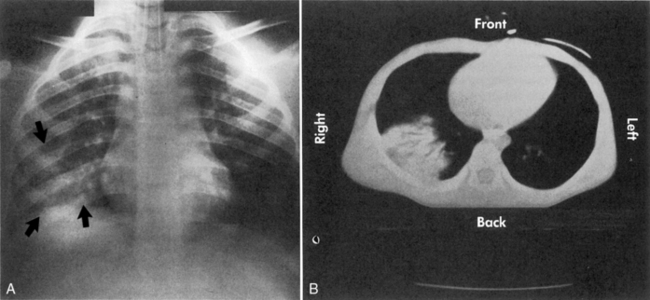

Tension pneumothorax develops from progressive air entry into the pleural space from the lung or airways; this air accumulation elevates intrapleural pressure, compresses the lung, and can compromise cardiovascular function. The lung on the side of the tension pneumothorax is partially collapsed, and severe hypoxemia develops (Fig. 19-3; see Fig. 10-7). Breath sounds and chest expansion on the side of the pneumothorax are decreased or absent.

image

Fig. 19-3 Chest radiograph showing tension pneumothorax. A, Right tension pneumothorax produces displacement of the mediastinum to the patient’s left side (arrow). Note the absence of rib fractures. This injury was sustained when the rear wheels of a car ran over the child’s right chest, and the tension pneumothorax was apparent on clinical examination. B, Reexpansion of the right lung is apparent after insertion of a chest tube. The mediastinum has shifted back to the midline. Opacification of the right lung is consistent with pulmonary contusion. The child is intubated and a nasogastric tube is in place. Note that the chest radiograph did not and should not delay thoracostomy.

(Chest radiographs courtesy of James Betts, Oakland, CA.)

A tension pneumothorax shifts the mediastinum away from the affected side. This shift reduces venous return to the heart and decreases cardiac output; neck vein distension may be observed. In addition, the point of maximal impulse and the trachea shift away from the tension pneumothorax,4 although the tracheal shift may be difficult to appreciate in infants and children. The resultant decrease in cardiac output and oxygen delivery are life threatening. The mediastinal shift can result in compression of the contralateral lung, further compromising oxygenation and ventilation.

A tension pneumothorax requires immediate needle decompression followed by tube thoracostomy. Needle decompression should be performed on the basis of clinical examination, and providers should not delay therapy to obtain a chest radiograph. A simple pneumothorax is treated with chest tube insertion.

A pulmonary contusion is a bruise on the lung resulting from lung parenchymal injury. Although a pulmonary contusion can be asymptomatic and diagnosed only on CT scan, it can cause respiratory compromise following major blunt chest trauma.13,44 A significant pulmonary contusion will cause hypoxemia, and opacification is visible on a chest radiograph or CT scan (see Figs. 19-3, B and 19-4).

Fig. 19-4 Pulmonary contusion on chest radiograph and computed tomography (CT) scan. A, Chest radiograph. Note the increased opacification in the patient’s right lower lung fields (arrows). Note the absence of rib fractures. B, CT scan from the same patient demonstrating opacification (white contusion is visible in the dark air density) of the right lower lung. The trachea is not visible in mediastinum, so opacification is below the area of bifurcation of the trachea into bronchi. This CT view is shot from below the area of contusion with a view in the cephalad direction. The patient’s right chest appears on the left side of this image, and the patient’s left chest is visible on the right side of this image. The front of the patient is the top of this image, and the patient’s back is at the bottom of this image; thus, the patient’s heart is anterior (visible as a white oval) and vertebral column is posterior.

An associated hemothorax typically suggests the presence of a more severe lung injury. Treatment includes supplementary oxygen and may require positive-pressure ventilation with oxygen support and positive end-expiratory pressure.